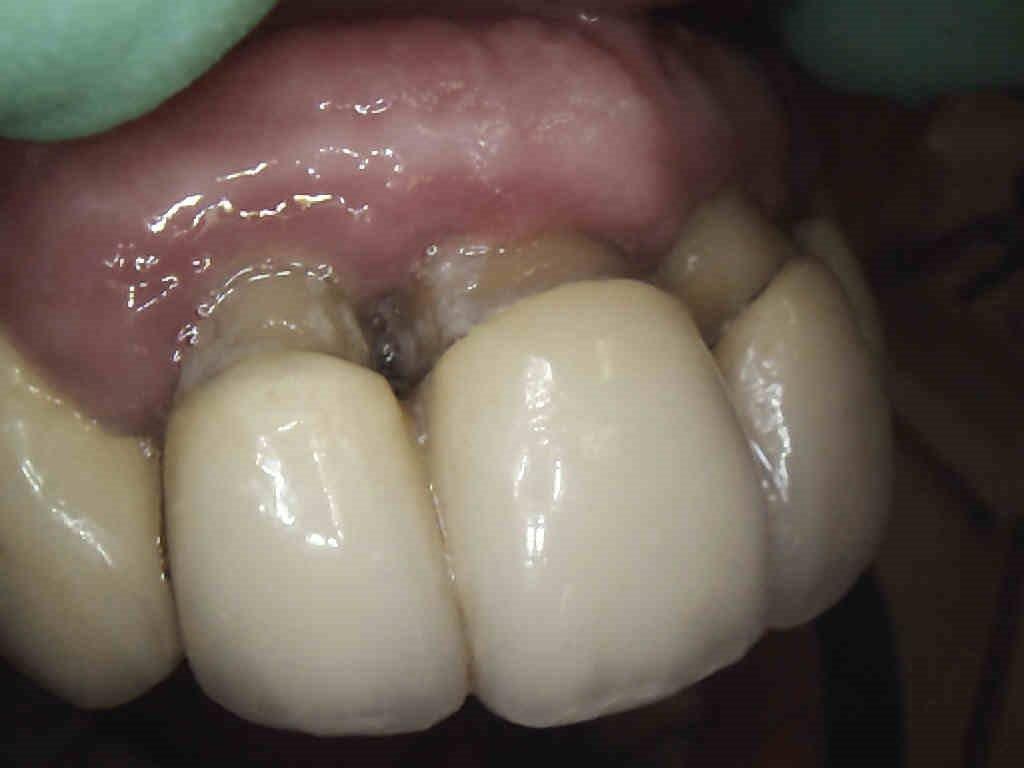

1 – Aspetto precura dell’arcata superiore sinistra